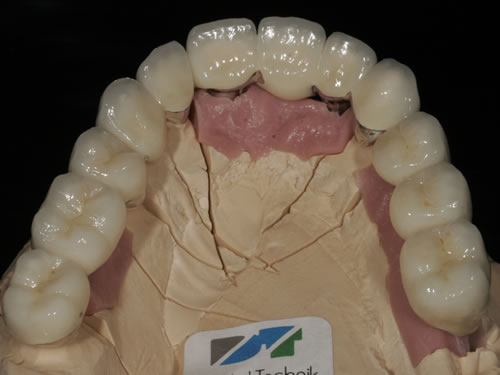

Abb. 3.25: Brücken vor der Eingliederung.

Abb. 3.26: Hybridversorgung einer reduzierten Oberkieferbezahnung auf 4 Zähnen und 3 Implantaten.